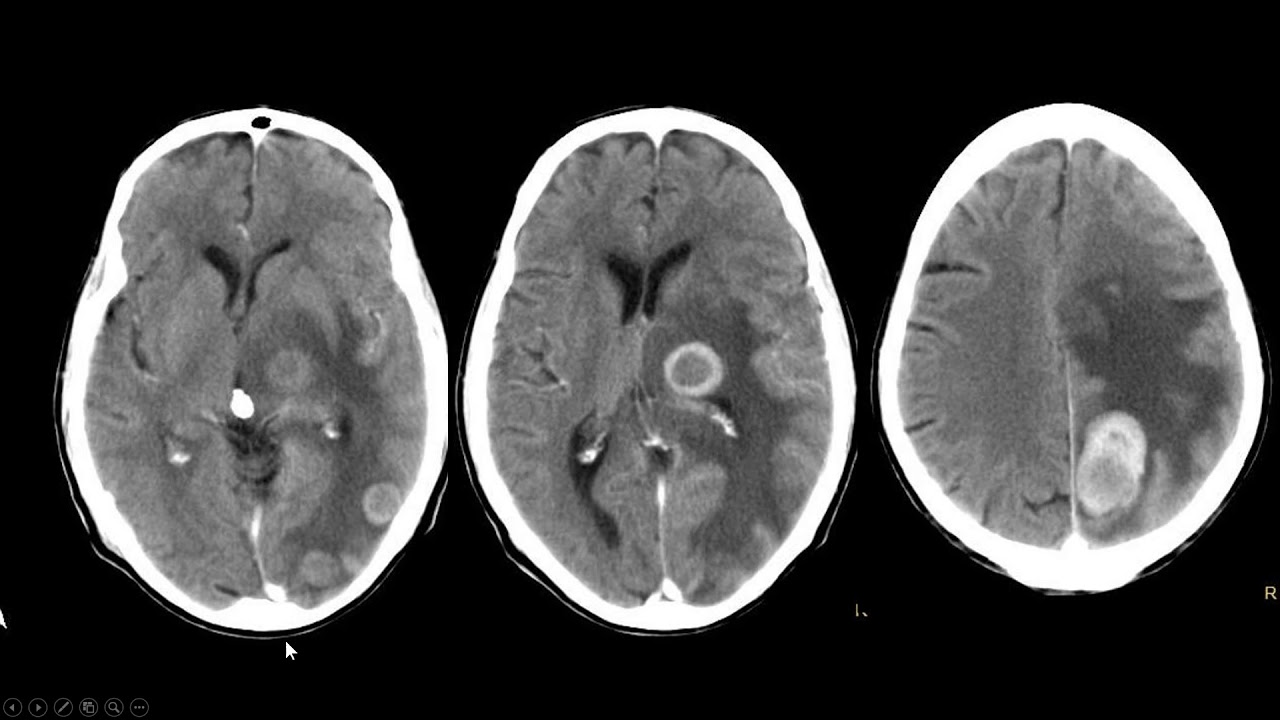

então ó acompanha aqui comigo eu tenho nessa criança que tá com cefaleia alteração da Marcha uma lesão Ó nessa região mais posterior aqui e no exame com contraste Dá para perceber que essa região é uma região específica do encéfalo do paciente é uma região que fica ali compreendida ó abaixo do território cerebelar então tem Thor cbbelar é uma reflexão das meninges que protege uma região chamada de força posterior não é bem que ela protege mas meio que ela faz a divisão o que tá abaixo dele é o cerebelo em si né a fossa posterior E

assim a gente tem um encéfalo Sul para territorial né os lobos temporal frontal parietal então aqui atrás ó a gente tem uma região que é chamada fossa posterior e um dos referenciais anatômicas que a gente pode usar para delimitar essa fossa é o território serebelar perceba então que existe um negócio estranho que não tem a mesma densidade não tem a mesma cor mesmo aspecto do parênquima encefálico como um todo e muito menos do próprio cerebelo aqui na fossa posterior perceba que tem uma área em que essa lesão ela é mais pretinha uma densidade que lembra

a densidade do próprio o licor como você pode ver aqui ó no terceiro ventrículo nos cornos temporais dos ventrículos laterais e nos cornos frontais dos ventrículos laterais então a densidade é igual a do líquido então é hipodenso semelhante ao líquido Então deve ser água deve ser um componente cisco dessa formação e eu tenho outro componente aqui que ele tem uma atenuação mais elevado seja não é que ele é branco mas ele é apenas é ele é um hipodenso mais um cinza um pouco mais claro ainda esses escuro mas é um cinza menos escuro do que

eu ligo percebe Isso aqui é uma atenuação que a gente chama de partes moles ou intermediária repara que depois que o injeto contraste nessa alteração aquela área que é mais cística ela continua pretinha igual mas a área que tinha densidade intermediária ela passou a exibir aumento da densidade ou seja ela eleva a sua atenuação porque ela tá apresentando real se pós contraste isso indica para mim que eu tô olhando a lesão sólida esse componente é sólido só que se a lesão tem um componente sólido e um componente cístico ela é o quê sólido cística ela

não tem não brilha no T2 brilha não é exatamente assim mas vamos simplificar por enquanto dessa forma Beleza então aqui ó tem um componente sólido cisco componente sólido ele tem um Realce e tá na fossa posterior de uma criança para você fechar sua principal suspeita diagnóstica nesse cenário aqui a única informação que falta você é garimpar desse exame já tá bem na sua frente que é a localização desse tumor repara que o tumor ele não está exatamente na linha média aqui na fossa posterior perceba que ele está lateralizado é como se o epicentro do tumor

tivesse no hemisfério cerebelar não no verme celebelar e se você ainda boia um pouquinho dessa coisa de hemisfério cerebelar verme celebelar procura aqui no canal com certeza tem alguma aula sobre anatomia do encéfalo na imagem tá você vai achar Dita e anatomia dos séculos você é radiologista você vai achar algo que vai te explicar sobre isso então ela tá no hemisfério se ele é uma lesão sólido cística é um componente sólido realça é uma criança que tá na fossa posterior tá Dá uma olhada comigo de um de perto nesses exames lesão sólidos cística componentes sólido

O componente sólido exibe Realce comprando cístico Continua sem realçar e na ressonância magnética a gente vê as mesmas coisas só que eu tenho que guardar é uma lesão que tá envolvendo predominantemente o hemisfério CDB lá direito lembra que na ressonância na tomografia no plano axial que é esse plano que a gente vê a rodela do paciente Esse é o lado direito e esse é o lado esquerdo você pode lembrar disso imaginando esse paciente deitado de barriga para cima e os pés dele virados para você se ele tá deitado de barriga para cima com os pés

virados para você esse só pode ser o lado direito e esse o lado esquerdo Então esse tumor é um clássico astrocitoma pilocítico juvenil se toma pilocítico [Música]